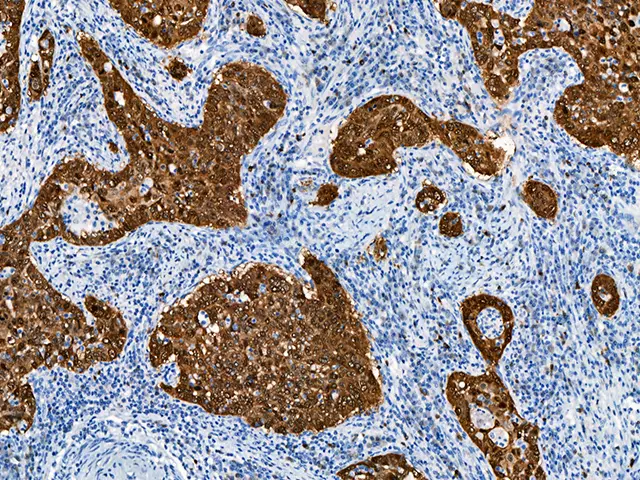

Pathologic Evaluation

Each specimen is meticulously examined by board-certified oral pathologists with specialized expertise.